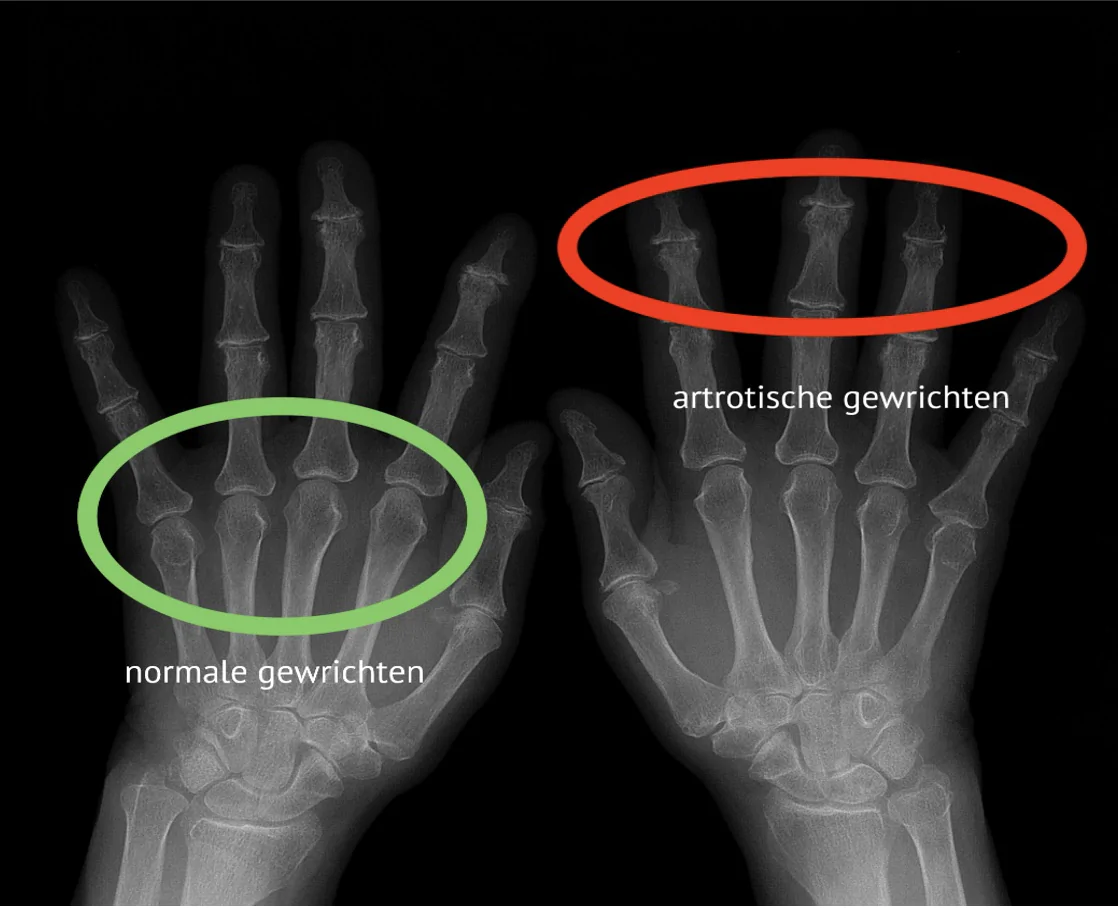

Uit recent onderzoek blijkt dat maar liefst 1,2 miljoen Nederlanders last heeft van artrose, en artrose in je handen is een van de meest voorkomende vormen - meer dan 500.000 Nederlanders hebben specifiek last van pijn in hand door artrose.

Vooral vrouwen boven de 50 jaar krijgen te maken met artrose hand symptomen zoals pijn in de vingers, stijfheid en verminderde handkracht.

Nog verontrustender: bij 75% van de mensen met artrose handen worden de klachten progressief erger als de onderliggende ontstekingsprocessen en kraakbeenafbraak niet worden aangepakt.

Waar Komt Artrose Handen Vandaan?

Handartrose ontstaat niet zomaar.

Het is het resultaat van chronische ontstekingsprocessen en kraakbeenafbraak in je handen en vingers, meestal door een combinatie van factoren die elkaar versterken.